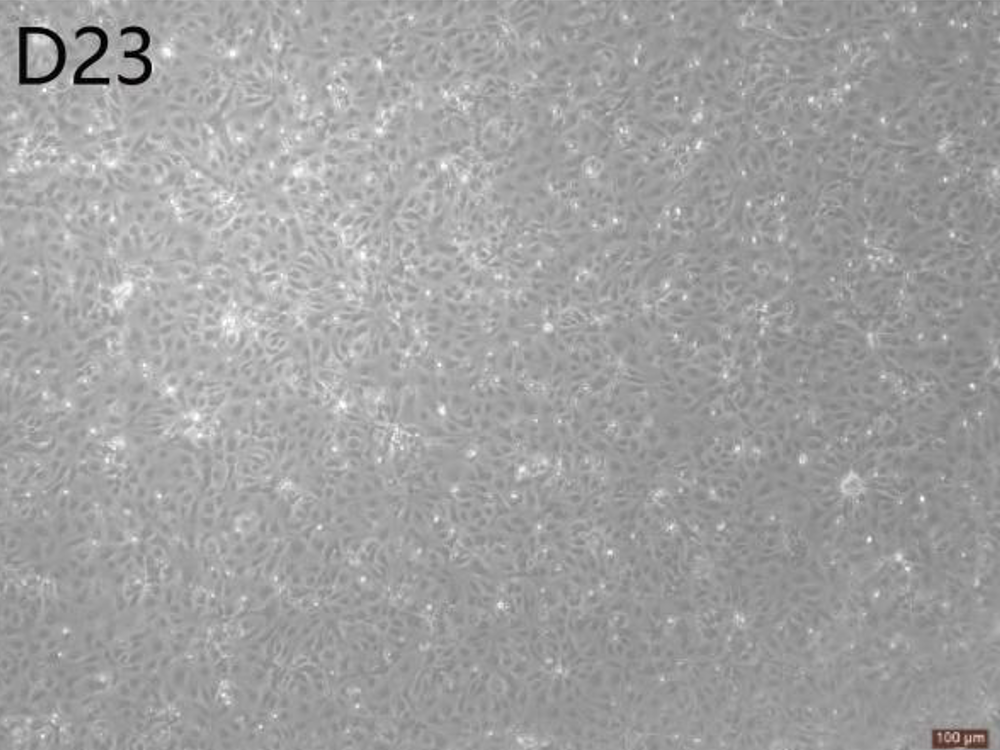

肾足样细胞在形态特征方面与体内足细胞相似,并且表达足细胞特异性标志物,如肾小球足细胞跨膜蛋白(Podocin)、足细胞和树突棘中的肌动蛋白相关蛋白(Synaptopodin)以及WT-1(Wilm'sTumorProtein),纯度高于90%。本产品可以广泛应用于基础研究、药物开发和临床转化研究等领域。